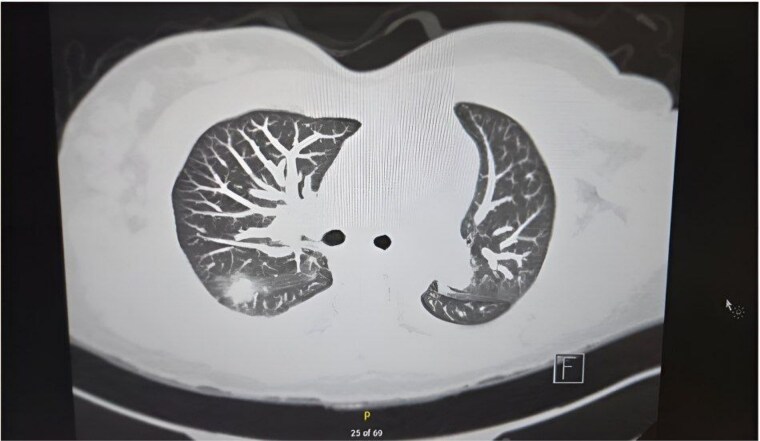

灾难性抗磷脂综合征(CAPS)是一种罕见的严重形式的APS,其特征是多器官血栓形成和细胞因子风暴。我们报告了一例复杂的病例,一名28岁的女性,她的COVID-19检测呈阳性,有深静脉血栓形成、肺栓塞和系统性红斑狼疮病史,并伴有潜在的APC,并发多器官CAPS。计算机断层扫描(CT)显示广泛的肺栓塞和右/左心室比值(RV/LV)升高。腹部及骨盆CT示胃炎、腹水及腹水、积液及双侧少量胸腔积液。尿液分析显示低水平的白蛋白,尿蛋白4+ g和高脂血症。实验室检查显示患者已发展为恶化的非少尿急性肾损伤和肾活检显示坏死性坏死。这是一个复杂的病例,有助于了解CAPS,并突出了其诊断和管理的挑战。

Catastrophic Antiphospholipid Syndrome (CAPS) is a rare serious form of APS characterized by thrombosis in multiple organs and a cytokine storm. We report a complex case of a 28-year-old female that tested positive for COVID-19 with a medical history of deep vein thrombosis, pulmonary embolus and systemic lupus erythematosus, with underlying APC, complicating her case of CAPS in multiple organs. Computed Tomography (CT) PE reveled extensive pulmonary emboli and an elevated right/left ventricular ratio (RV/LV). CT of the abdomen and pelvis showed gastritis, ascites and anasarca, fluid accumulation and small bilateral pleural effusions. Urinalysis showed low levels of albumin, urine protein 4+ g, and hyperlipidemia. Laboratory test indicated that the patient has developed a worsening non oliguric acute kidney injury and renal biopsy revealed necrotizing. This is a complex case that contributes to the understanding of CAPS and highlights the challenges of its diagnosis and management.